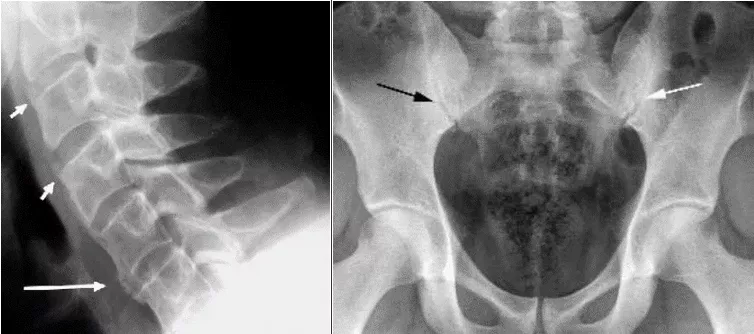

Аксиальное поражение при ПсА имеет ряд особенностей. В 25% случаев сакроилиит и спондилит при ПсА протекают латентно (без боли). Сакроилиит при ПсА, в отличие от АС, – часто асимметричный. Для ПсА характерно медленное рентгенологическое прогрессирование сакроилиита, полный анкилоз КПС на фоне длительного течения заболевания отмечается значительно реже, чем при АС (до 6% пациентов). При ПсА возможно поражение позвоночника (рентгенологические признаки спондилита) без сакроилиита, чего не наблюдается при анкилозирующем спондилите (АС). При ПсА, в противоположность АС, синдесмофиты чаще малочисленны, расположены асимметрично, в случайном порядке, не вдоль ≪последовательно идущих≫ позвонков, имеют больший размер и объемную форму, встречаются паравертебральные синдесмофиты (ПВС) – особый вариант обызвествления передней продольной связки позвоночника. ПВС представляют собой широкие грубые оссификаты, которые отстоят от края тела позвонка. Также наблюдаются краевые синдесмофиты (КС) – вертебральные оссификаты, отходящие от края тела позвонка вверх. КС могут образовывать ≪мостики≫ между позвонками. КС и ПВС ориентированы вверх (сужения смежного межпозвонкового промежутка не наблюдается). Это отличает их от выявляемых при дегенеративных заболеваниях позвоночника остеофитов (или спондилофитов), которые ориентированы горизонтально, около измененного диска (сужение межпозвонкового промежутка). Нередко, несмотря на существенные рентгенологические изменения, у больных отсутствуют заметные функциональные нарушения, что также отличает спондилит при ПсА от поражения позвоночника при АС. Спондилит и сакроилиит могут наблюдаться при любой клинической форме ПсА.

Рисунок 10. Слева: Рентгенограмма шейного отдела позвоночника в боковой проекции. Псориатический спондилит. Синдесмофиты (короткие стрелки) и обызвествление (длинная стрелка) передней продольной связки в шейном отделе. Справа: Рентгенограмма таза. Двусторонний асимметричный сакроилиит III стадии слева и I стадии справа (черная стрелка). Видны широкая зона остеосклероза (>3 мм), сужение и неровность щели КПС, частичный анкилоз (белая стрелка). Сакроилиит считается асимметричным, когда между правым и левым КПС различия больше, чем на одну стадию.